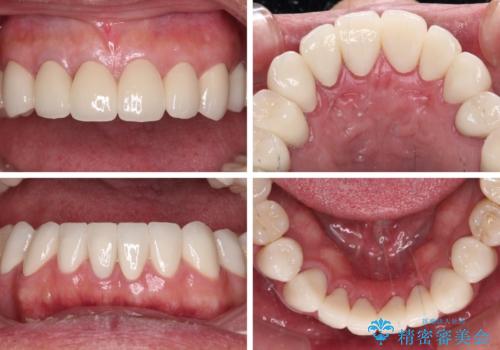

憧れの白い歯に 全顎セラミック治療

- 60歳を越え、黄ばんだ前歯をセラミッククラウンできれいな口元にしたいとのことで来院された患者様です。

診察したところ、前歯は反対咬合であり、その影響で抜歯が必要な奥歯があることが分かりました。

抜歯が必要な奥歯は、インプラント並びにブリッジにより補綴を行い、上下前歯は反対咬合を改善させるように補綴治療を行うこととしました。

健全な歯を削ってセラミッククラウンに置き換えることは、本来避けるべき治療と考えますが、今回は①患者様が60歳を越えていること、②要改善の咬合により抜歯が必要な奥歯があること、③反対咬合の前歯改善の手段としてセラミック治療が選択肢にあることなどから、全顎的なセラミック治療を行うこととしました。